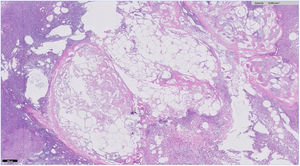

An 83-year-old woman was admitted for acute pancreatitis after consultation for epigastralgia and hyperamylasemia (13,370 U/l; normal range 20-120). Two days later, she presented with nonulcerated, painful, erythematous-purplish subcutaneous nodules on her legs and arms (Fig. 1). Ultrasound revealed inflammation of the subcutaneous cell tissue. A nodule was biopsied and confirmed pancreatic panniculitis (Fig. 2). Pancreatic panniculitis, or pancreatic fat necrosis, is a rare skin manifestation (< 3%) of pancreatic diseases. It can precede the diagnosis of pancreatic pathology, and so pancreatic disease screening should be carried out in patients that present with no abdominal symptomatology. Pancreatic panniculitis is clinically indistinguishable from other types of panniculitis, but the histologic findings are pathognomonic: lobular panniculitis with extensive necrosis of adipocytes and “ghost cells” (adipocytes that have no nucleus and a fine, granular, basophilic deposit due to calcium accumulation). Progression parallels that of pancreatic disease.